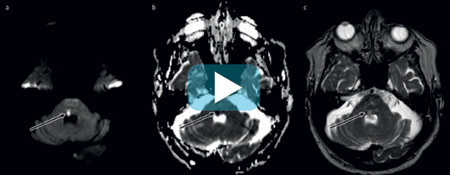

En tidligere frisk mann i 80-årene utviklet akutte synsproblemer med dobbeltsyn i alle blikkretninger. Han følte seg ustø og kastet opp flere ganger. Ved innleggelse i nevrologisk avdeling ble det påvist en kompleks øyemotilitetsforstyrrelse med konjugert blikkparese mot høyre og internukleær oftalmoplegi mot venstre (video). CT caput ved innkomst viste kun lette hypodense forandringer, forenlig med kronisk iskemi. MR med diffusjonsvektet serie viser følgende: a) hyperintenst signal (pil) dorsalt i hjernestammen på høyre side (summasjonsbilde), b) lavt signal i samme lesjon på ADC-kartet (Apparent Diffusion Coefficient) (pil) og c) lett hyperintenst signal på T2-vektet serie (pil). Funnet er forenlig med cytotoksisk ødem og akutt hjernestammeinfarkt i den paramediane pontine retikulærsubstansen. Dette kunne forklare pasientens symptomer.